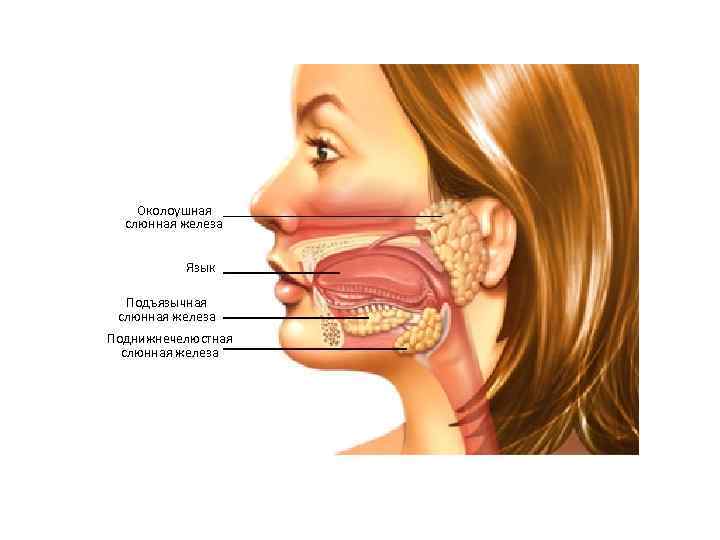

Околоушная слюнная железа Язык Подъязычная слюнная железа Поднижнечелюстная слюнная железа